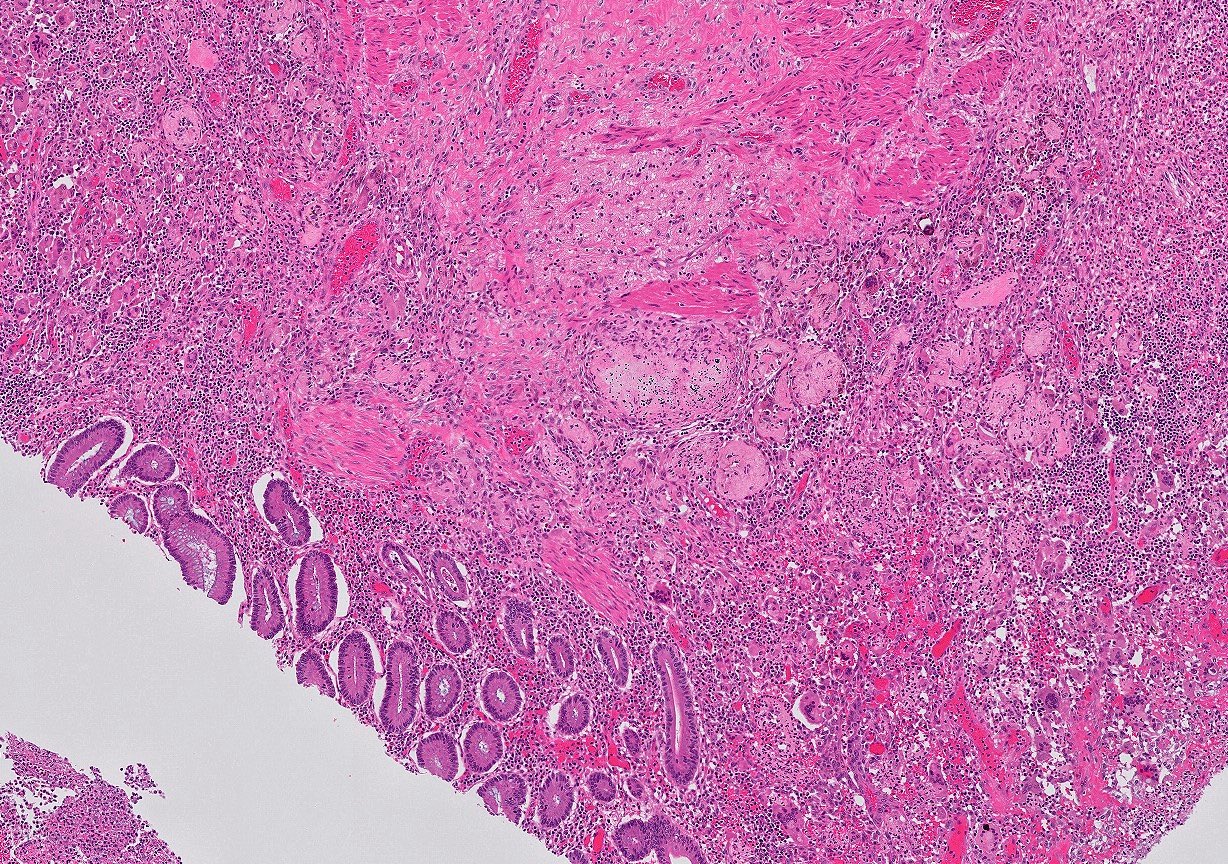

Microscopic (histologic) description

- Mucosa may be normal to markedly abnormal

- Expansion of lamina propria by lymphoplasmacytic infiltrate (more prominent in basal half)

- Lymphoglandular complexes, mucin depletion, focal Paneth cell metaplasia (in chronic cases) may be seen (J Clin Gastroenterol 2004;38:S11)

- Muscularis mucosa extends towards surface between elongated crypts

- Shortening of the affected bowel and hypertrophy of circular muscle layer (myochosis) leads to exaggerated mucosal folds (Am J Surg Pathol 1991;15:871)

- Some cases can show lamina propria fibrosis, crypt elongation on the tips of prominent mucosal folds, like mucosal prolapse syndrome in rectum and anus (J Clin Gastroenterol 2008;42:1137)

- Hemosiderin deposition in submucosa may be seen (StatPearls: Diverticulosis [Accessed 21 April 2022])

- Can mimic inflammatory bowel disease

- Hyperplasia of lymphoid aggregates is one of the earliest signs of diverticulitis

- Cryptitis, crypt abscesses, peridiverticular abscess and fistulas may be superimposed on this background in acute diverticulitis

- Tracking abscesses can spread longitudinally or circumferentially and can cause diverticular colitis

- Persistent localized inflammation can lead to phlegmon which is a thickened, firm segment of bowel wall that can lead to strictures and acute or subacute large bowel obstruction (Best Pract Res Clin Gastroenterol 2002;16:543)

Microscopic (histologic) images

Contributed by Bindu Challa, M.D. and Martha M. Yearsley, M.D.